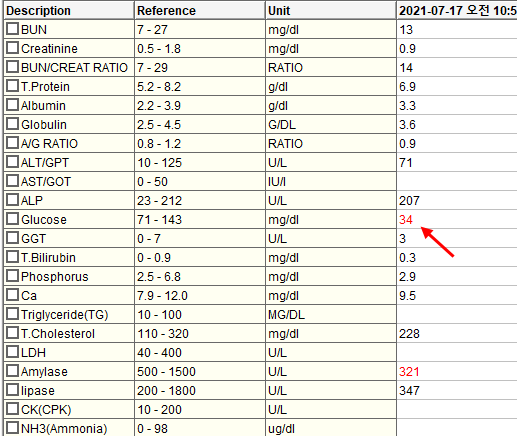

<혈액검사 상 확인된 매우 낮은 수준의 혈당>

대부분의 검사에서 큰 이상이 확인되지 않았지만, 심각한 수준의 저혈당이 확인되었습니다. 보통의 강아지들은 이정도 저혈당이면 일어서지도 못할 수준이었는데요, 발작하거나 쓰러져 있어야 정상이지만 메리는 겉으로 보기엔 약간 기운 없어 보이는 정도로 큰 이상이 보이지 않았습니다.

잠실ON동물의료센터의 내과 의료진은 혈당과 관련한 검사를 진행하였습니다. 검사결과, 메리는 지속적인 저혈당을 보였으며 혈중의 인슐린 농도가 극도로 높았음이 확인되었습니다.